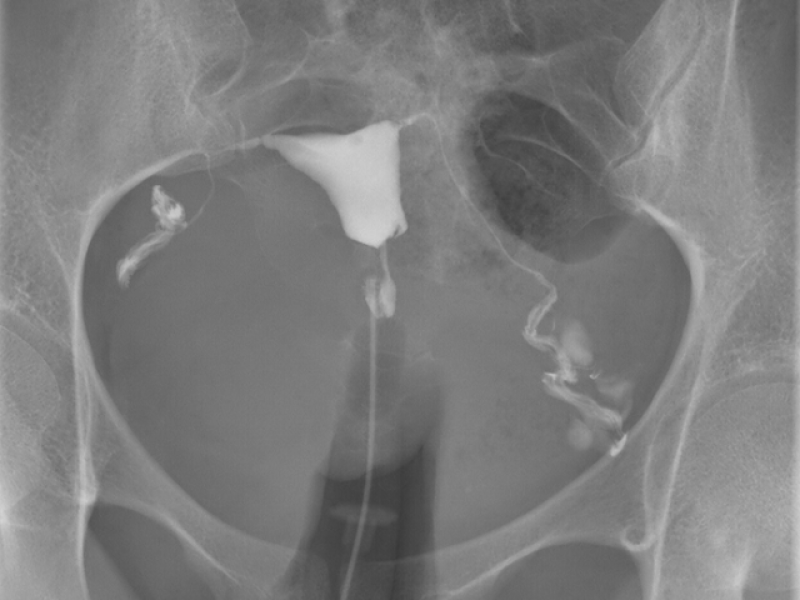

L’hystérographie ou test HSG, est un examen utilisé pour évaluer la perméabilité des trompes de Fallope (conduits reliant les ovaires à l’utérus, où se déroule généralement la fécondation) et la cavité utérine. Cet examen sert à comprendre les causes potentielles de l’infertilité.

L’examen doit être réalisé pendant la première phase du cycle menstruel, soit juste après la fin des règles et avant le début de l’ovulation. La durée de la procédure est généralement comprise entre 15 et 30 minutes.